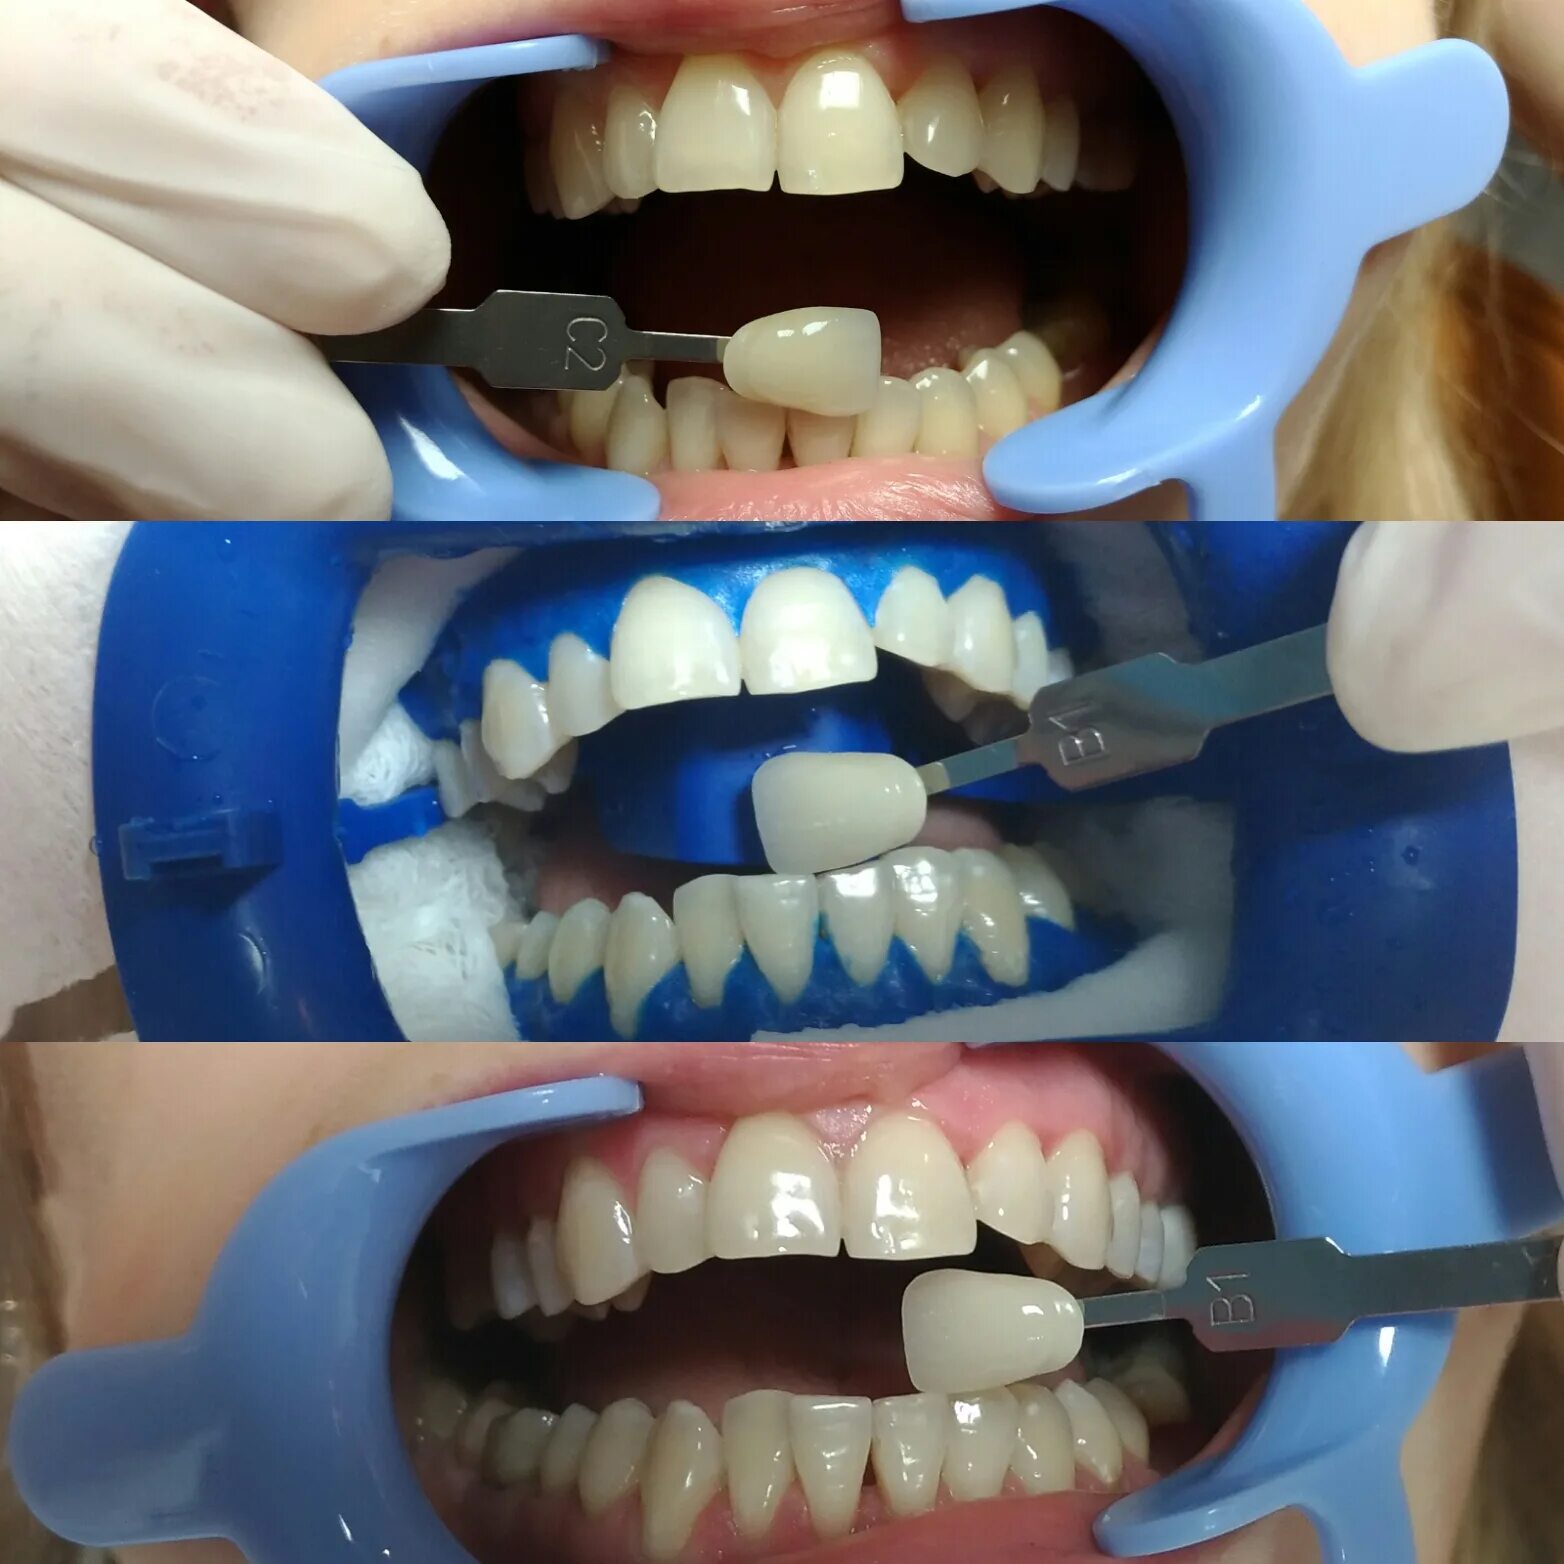

Удалить зуб митино